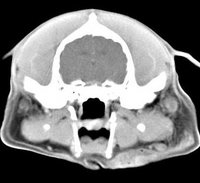

imágenes de TC en el perro | ||||||||||

ejemplo de imágenes de TC en el perro. Nótese la celulitis en la región parotídea izquierda | ||||||||||